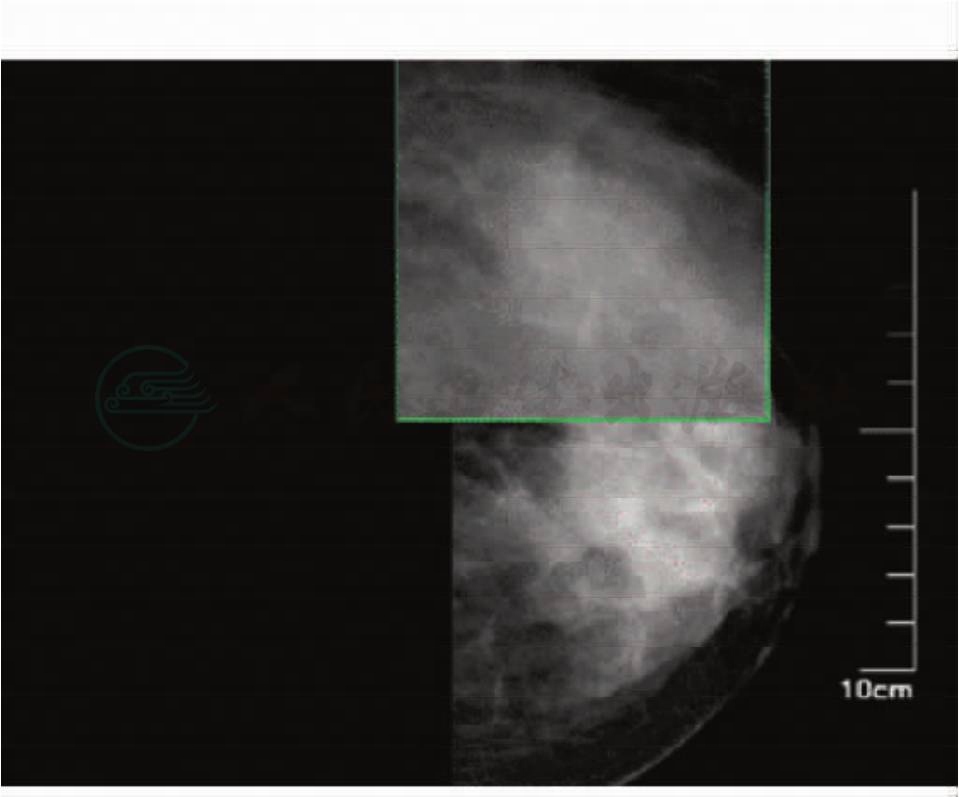

乳腺X线片(图1):左乳肿物,伴簇状微钙化,BI-RADS: 4B。

图1 乳腺癌乳腺X线片